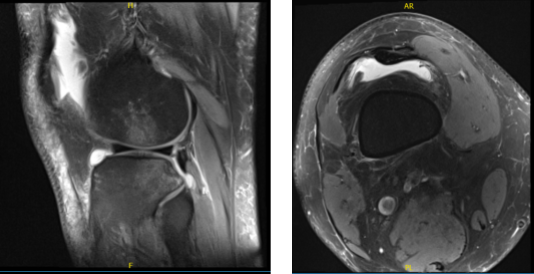

X-ray reviewed and discussed and suspected to have a tear meniscus. We agreed to have an MRI to see the reason behind it. His MRI Impression as follows: There is an acute tear of the mid anterior cruciate ligament with contusions in the lateral femoral condyle and posterior lateral tibial plateau.

There is a nondisplaced subcortical fracture of the posterior lateral tibial plateau. There is also contusion in the medial femoral condyle. Radial tear of the posterior horn of the medial meniscus at the level of the meniscal root attachment with extrusion of the body.

Lateral subluxation of patella with moderate chondromalacia in the apex. Large joint effusion with synovitis. There is a strain of the popliteus muscle.

MRI of knee